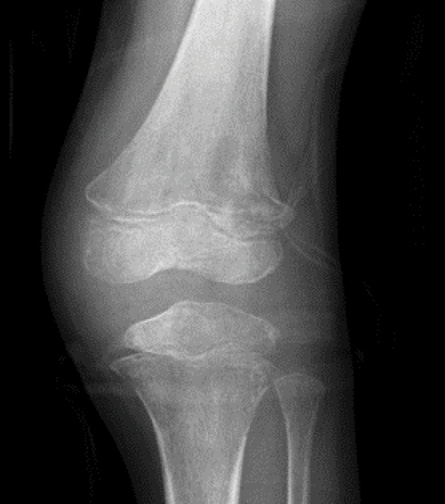

The chest X-ray and abdominal ultrasound images were normal. However, the X-ray of the left knee showed heterogeneous lucencies with diffuse erosions [Figure 1].

Figure 1: X-ray image of the left knee showing heterogeneous lucencies of the distal femoral metaphysis, proximal tibial metaphysis, and proximal fibular metaphysis with diffuse erosions.